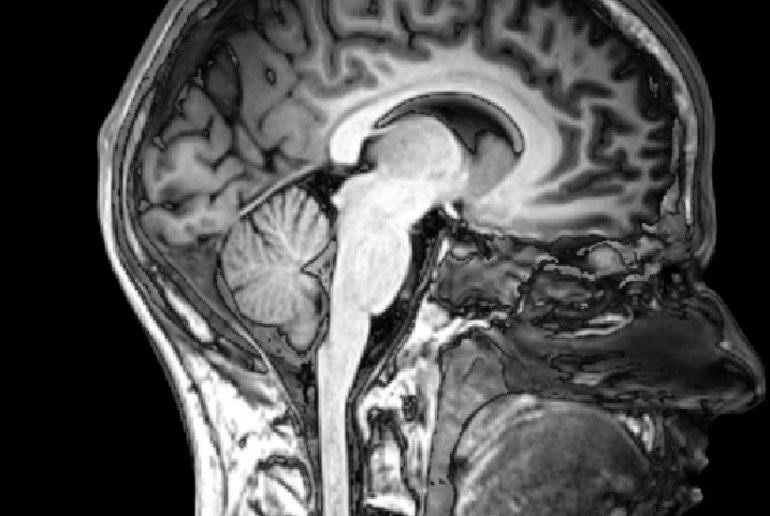

Enhanced Brain Image Data Quality in MRI –

Brain Imaging or Neuroimaging is conducted to assess brain disorders and ensure proper functioning. Brain imaging helps diagnose brain diseases and also improve research pertaining to the human brain. Even though these are just some of the many great advantages of brain imaging, MRI (Magnetic Resonance Imaging) faces huge issues during the process. Reduction in data quality arises, as the patient moves his/her head during MRI scan, it hinders brain analysis & results into wrong diagnosis. With ML assistance & software such as FIRMM, that helps monitor brain-related data in real-time and provides metrics on data quality. Developed under Linux OS, and works only mainly in Ubuntu and CentOS platforms.